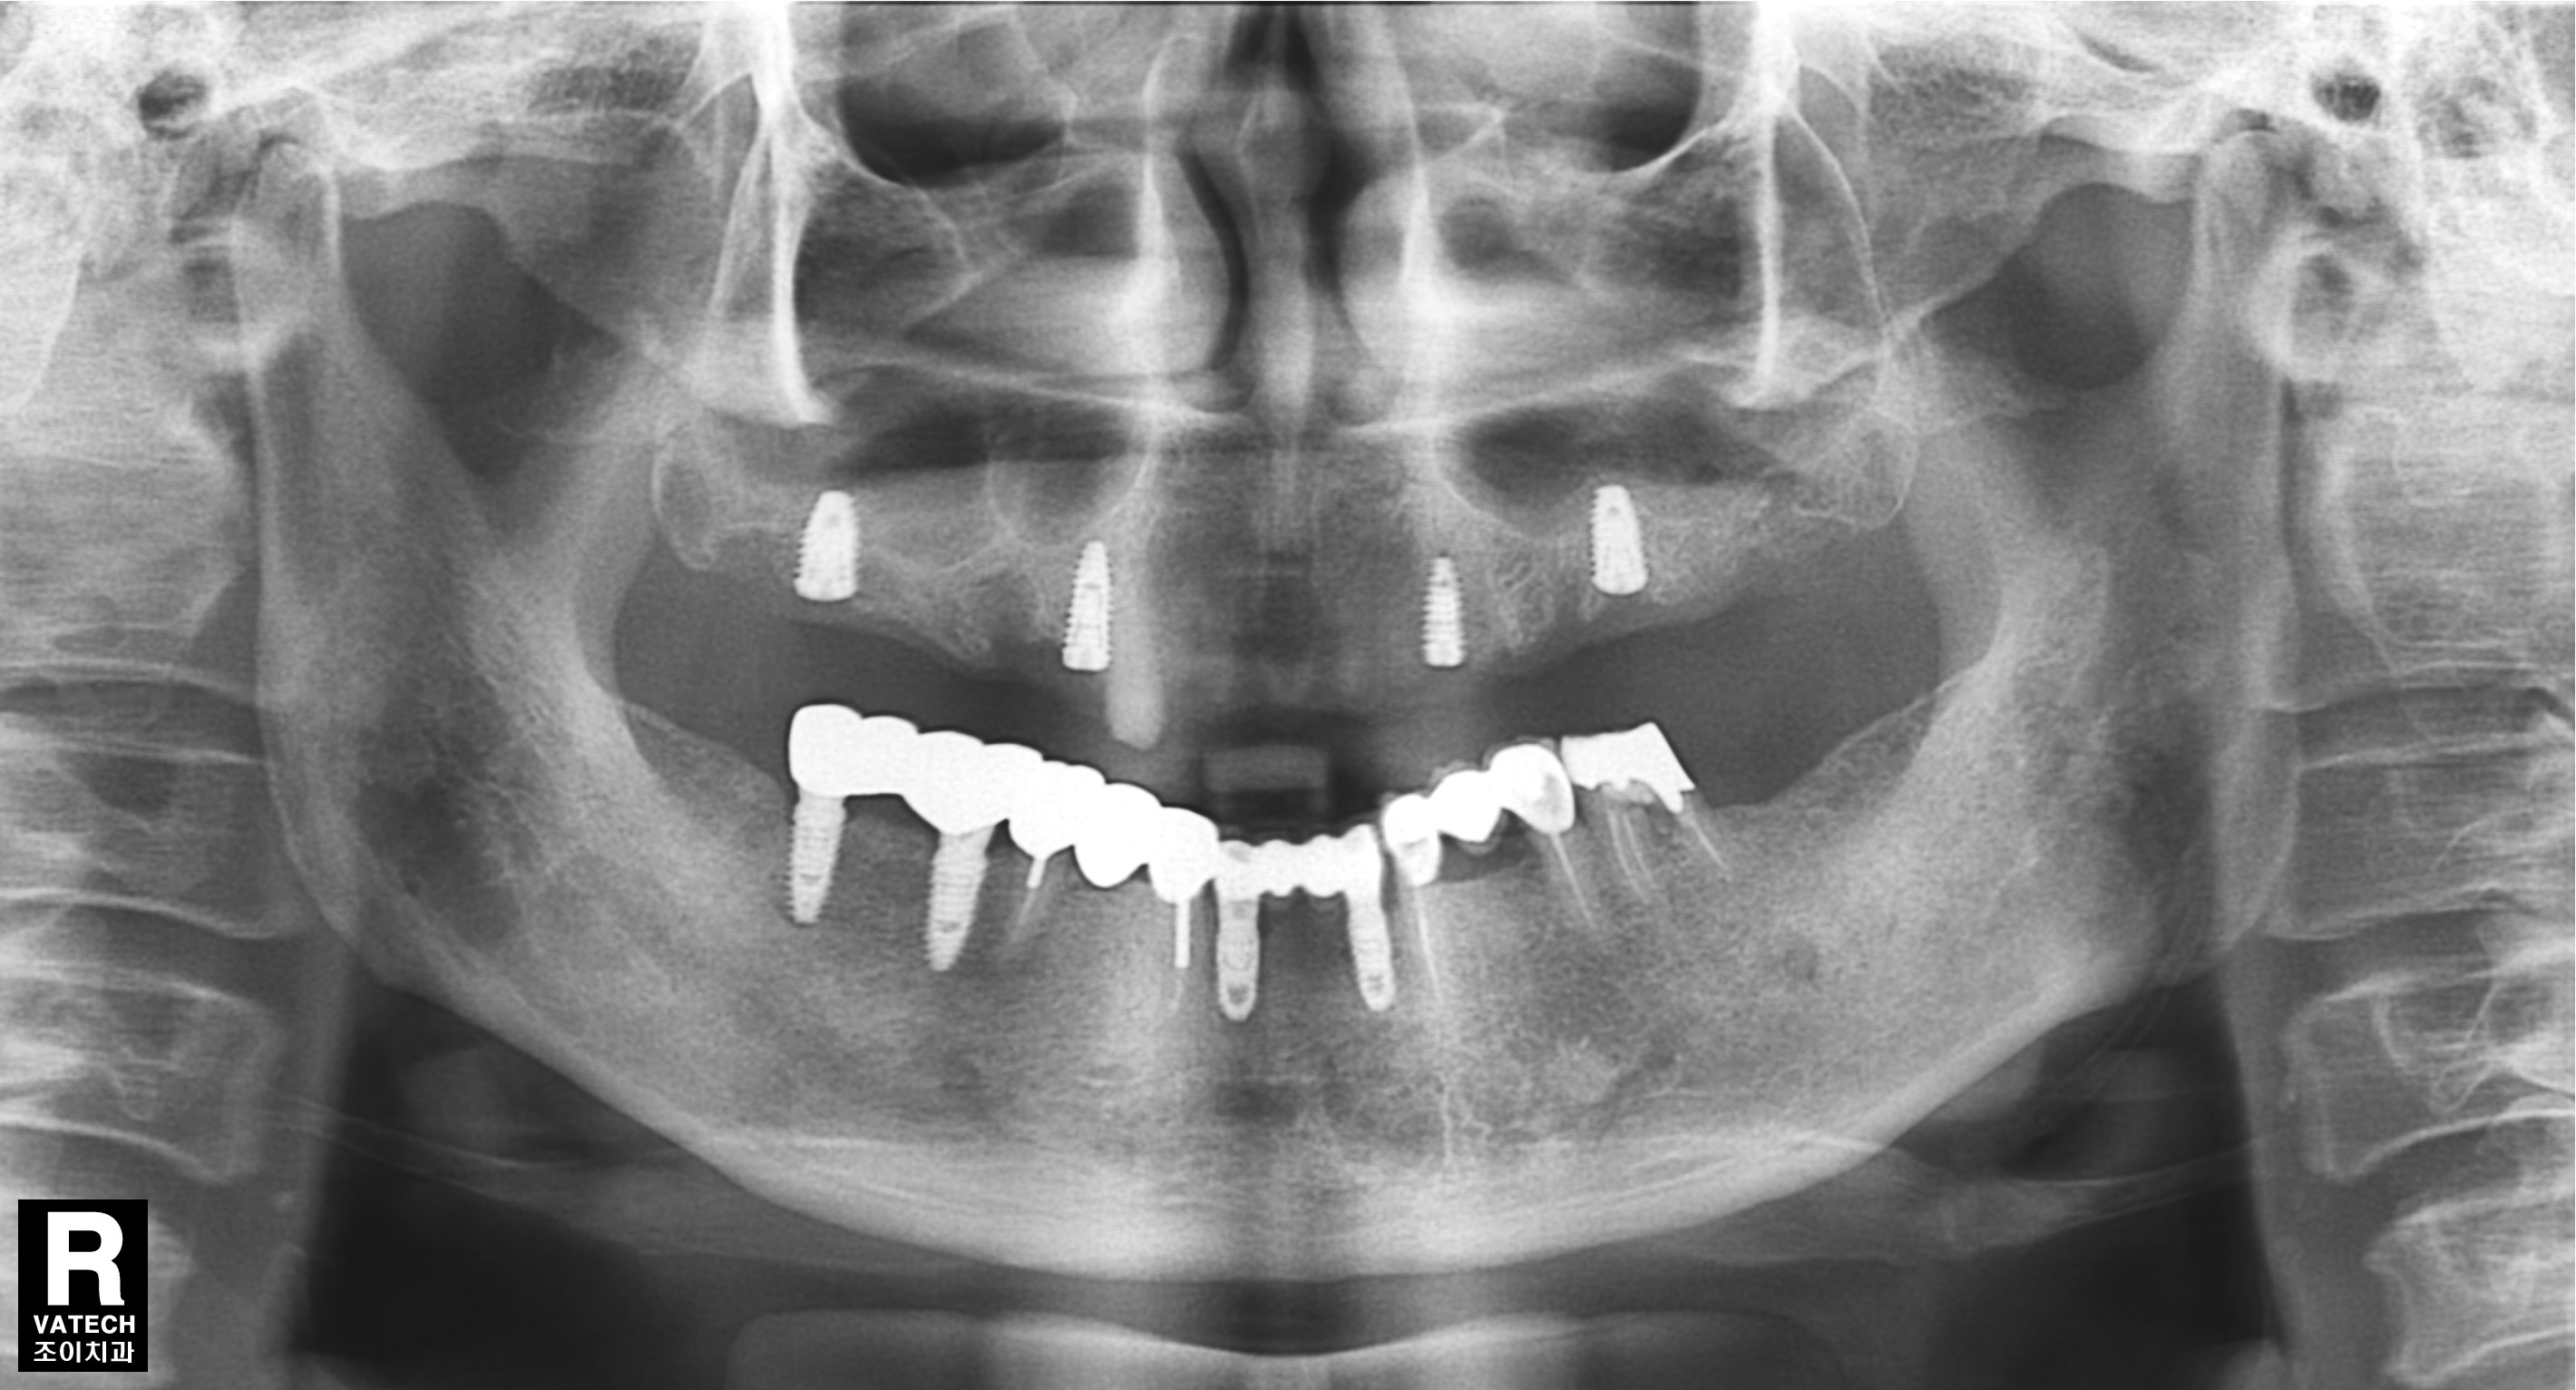

임플란트 지지틀니입니다.

임플란트에 똑딱이 같은 장치를 달아서 틀니를 쓰기 편하게 하는 방법입니다.